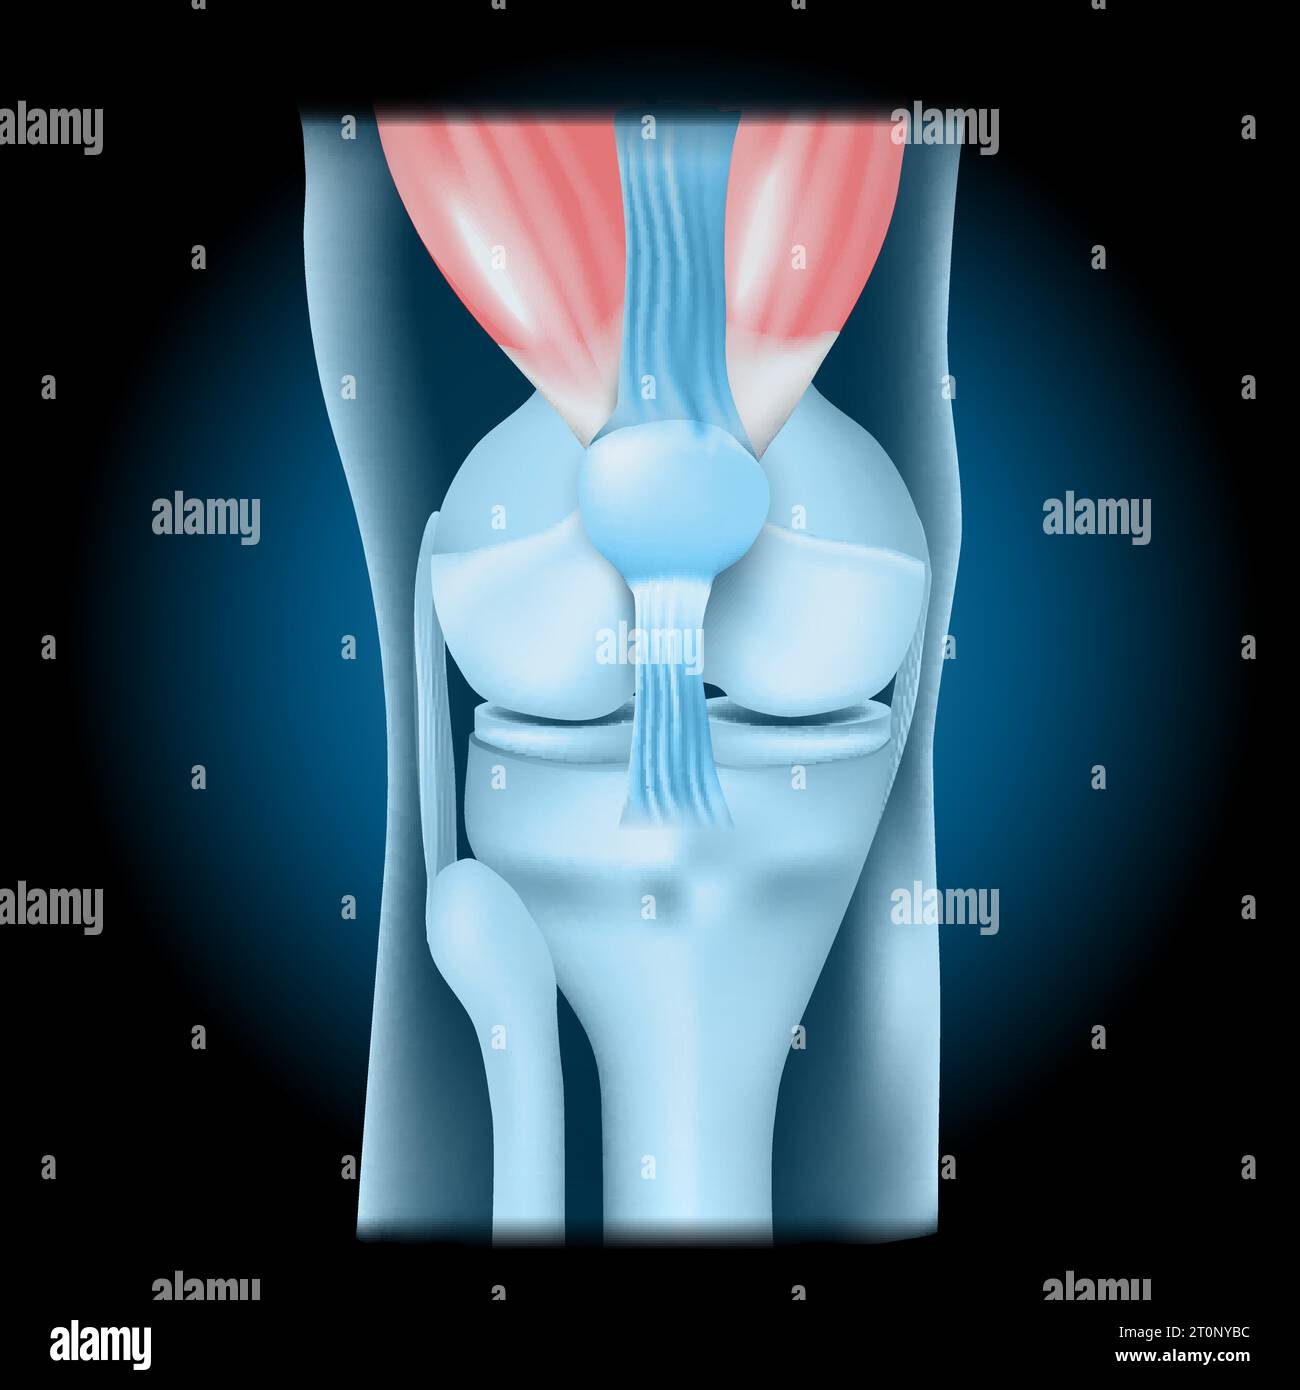

Knee joint with Quadriceps. Front view of human knee with glowing effect. Realistic transparent blue joint on dark background. vector illustration lik Stock Vectorhttps://www.alamy.com/image-license-details/?v=1https://www.alamy.com/knee-joint-with-quadriceps-front-view-of-human-knee-with-glowing-effect-realistic-transparent-blue-joint-on-dark-background-vector-illustration-lik-image568424624.html

Knee joint with Quadriceps. Front view of human knee with glowing effect. Realistic transparent blue joint on dark background. vector illustration lik Stock Vectorhttps://www.alamy.com/image-license-details/?v=1https://www.alamy.com/knee-joint-with-quadriceps-front-view-of-human-knee-with-glowing-effect-realistic-transparent-blue-joint-on-dark-background-vector-illustration-lik-image568424624.htmlRF2T0NYBC–Knee joint with Quadriceps. Front view of human knee with glowing effect. Realistic transparent blue joint on dark background. vector illustration lik